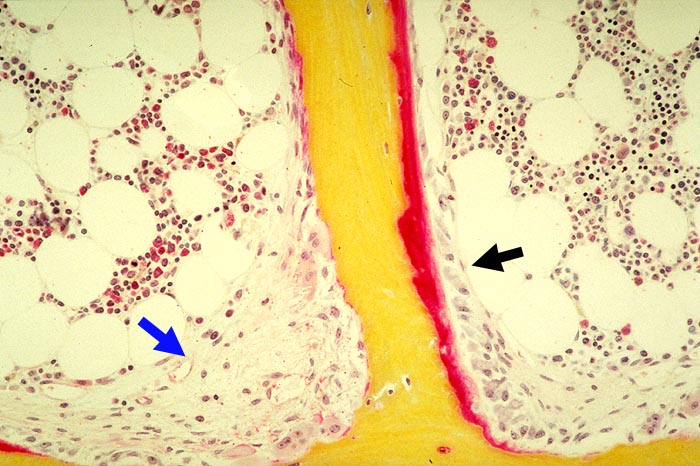

Renale Osteopathie: tunnellierende Fibroosteoklasie, Osteoidose

Stark erhöhter Spongiosaumbau: Resorptionslakune mit Osteoklasten und endostaler Fibrose (Fibroosteoklasie). Osteoblasten- und roter Osteoidsaum (Osteoidose).

Sekundärer Hyperparathyreoidismus bei chronischer Niereninsuffizienz.